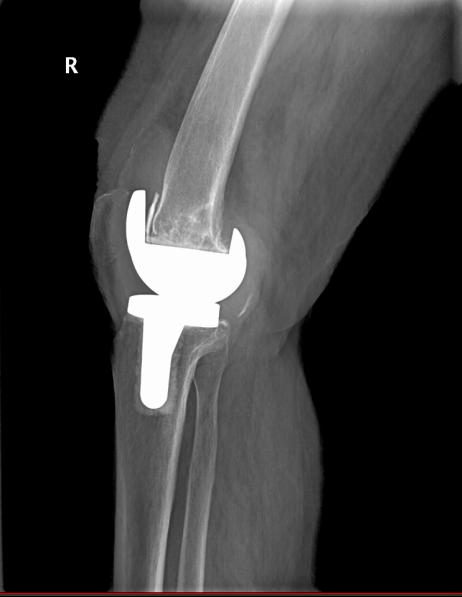

8年前刘奶奶在外院行双膝人工关节表面置换术,术后恢复良好,近2年来反复出现右膝关节疼痛,多次在柳州各大医院门诊及住院诊治,在药物治疗的干预下膝关节疼痛、肿胀时好时坏,来我院门诊诊断右膝关节置换术后感染、假体松动,入住我院关节外科/运动医学科。

图2 X线